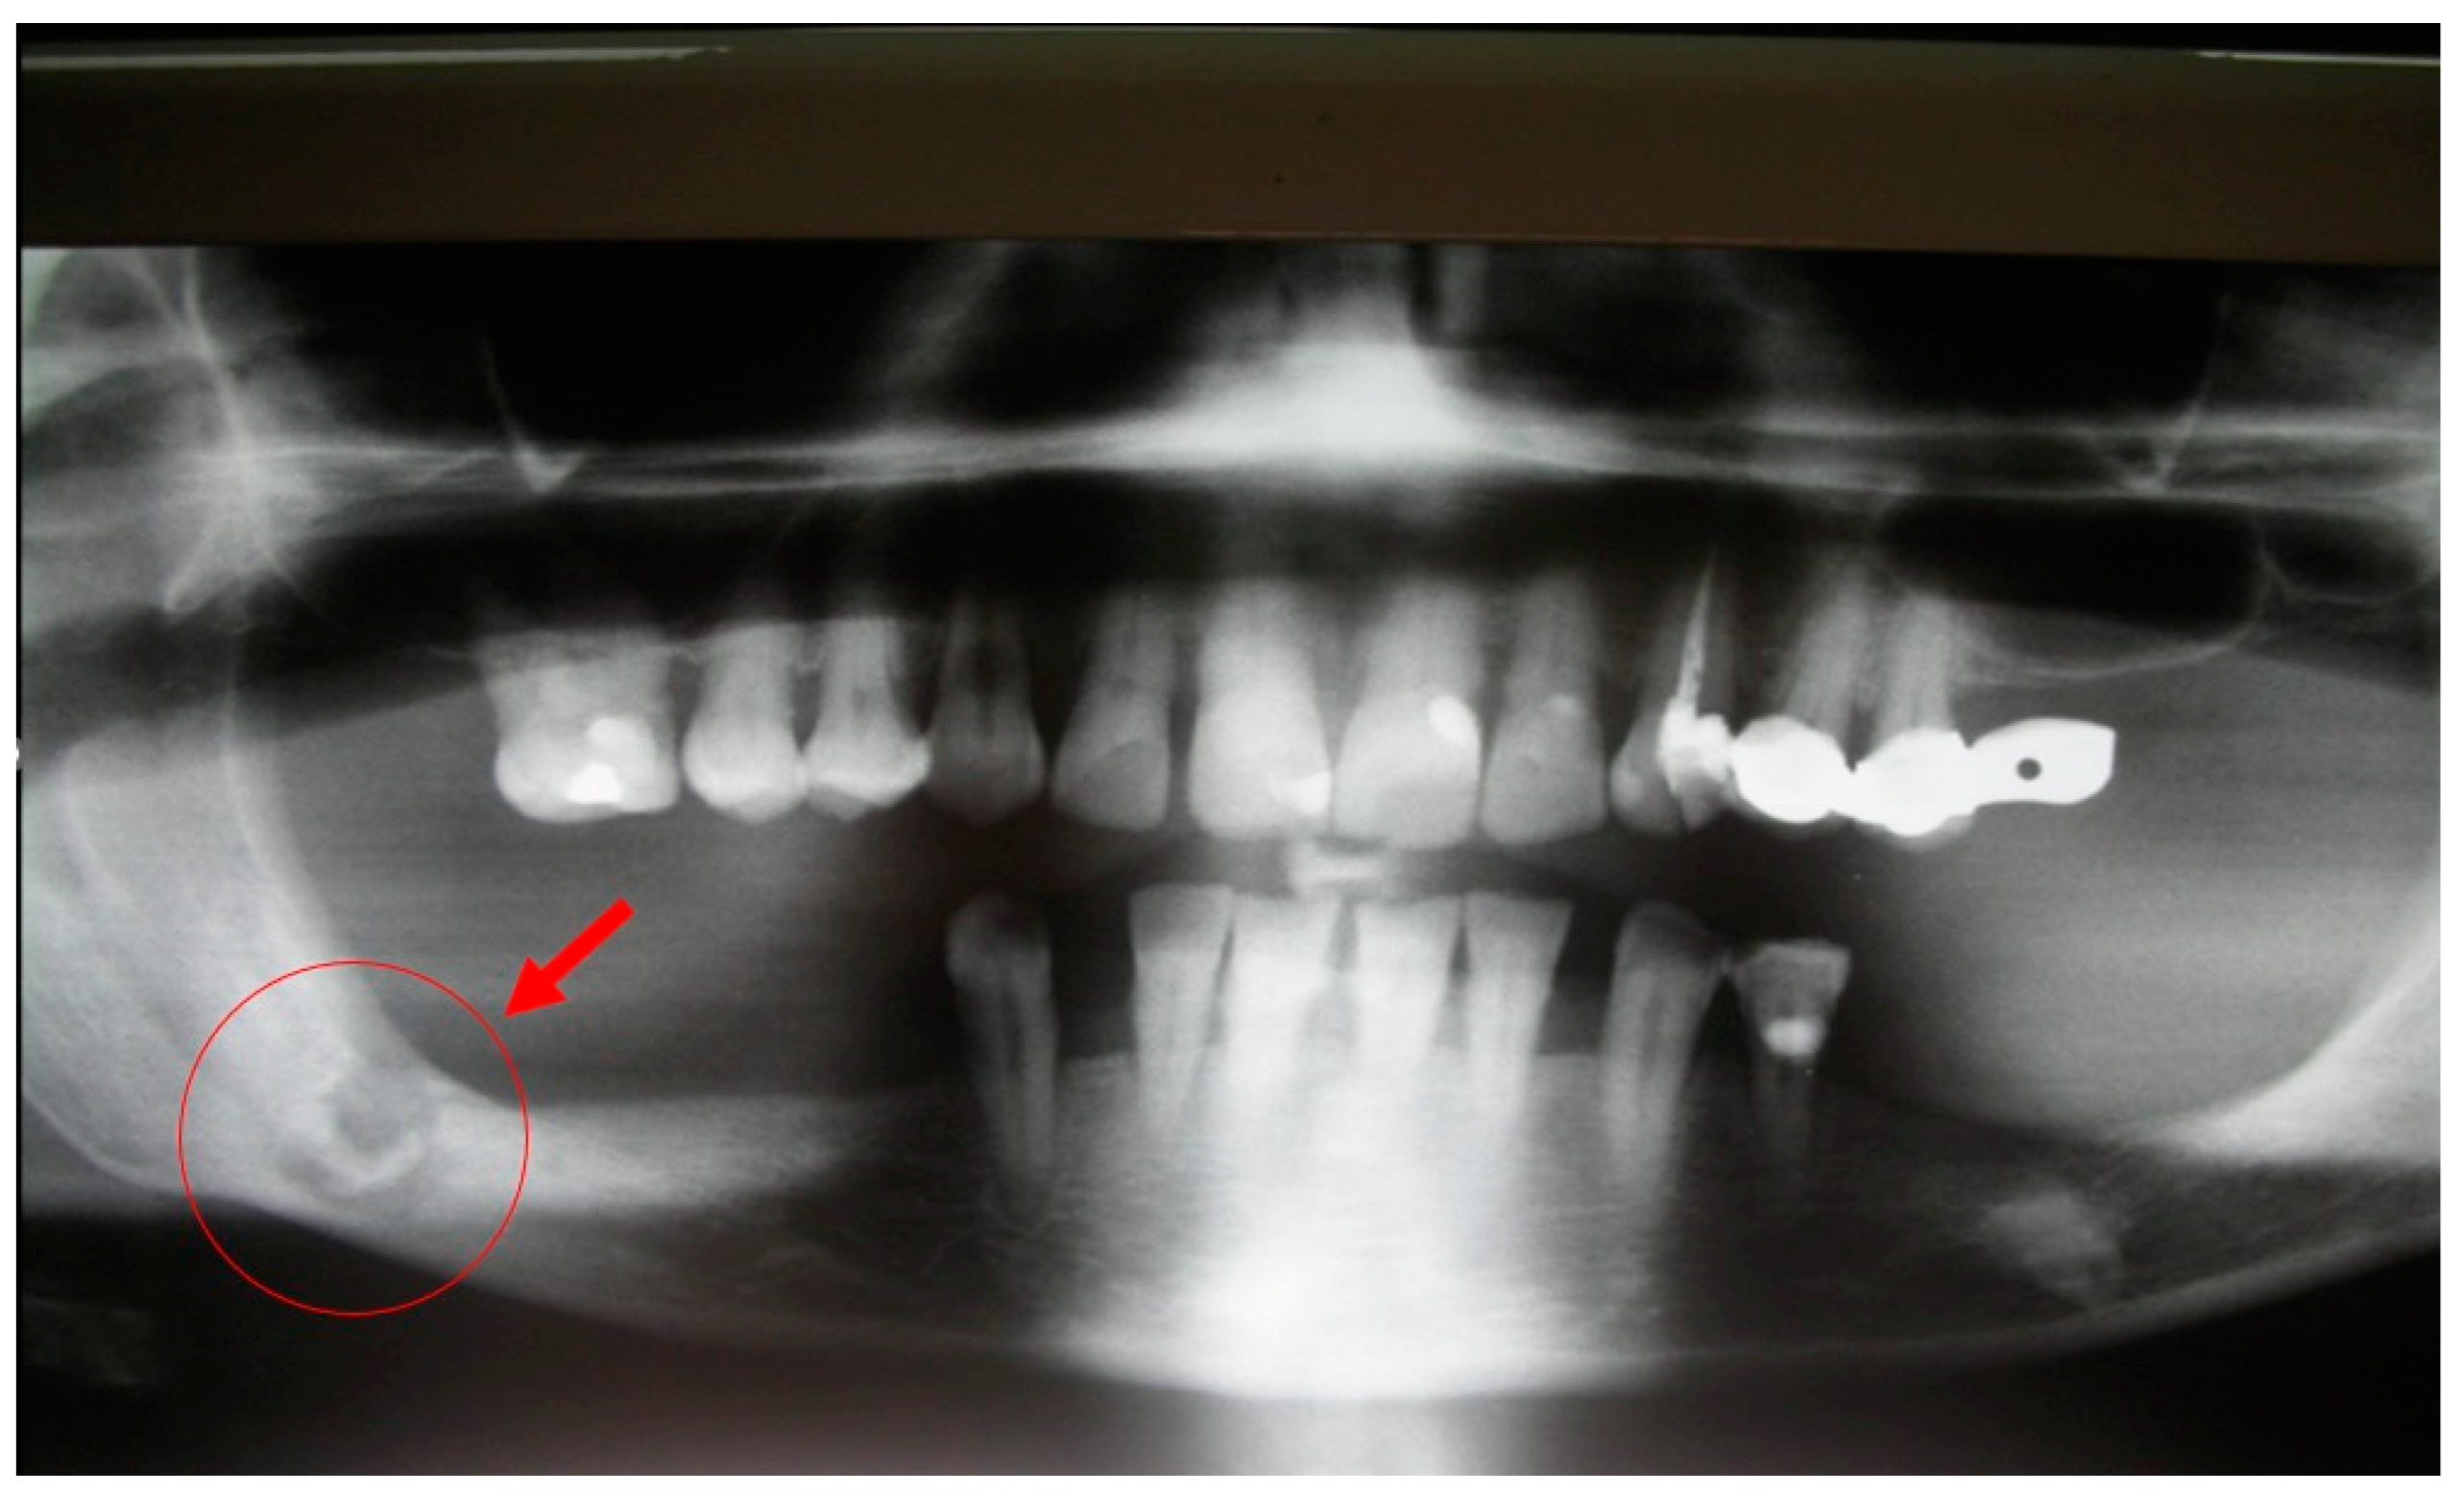

5.1. Case Report 1

A 61-year-old female patient developed MRONJ after the administration of intravenous ARA. The lesion has been radiologically identified through orthopantomography (OPT) and CBCT (Figure 8 and Figure 9).

Figure 8.

Initial lesion showed in OPT pointed by the circle.